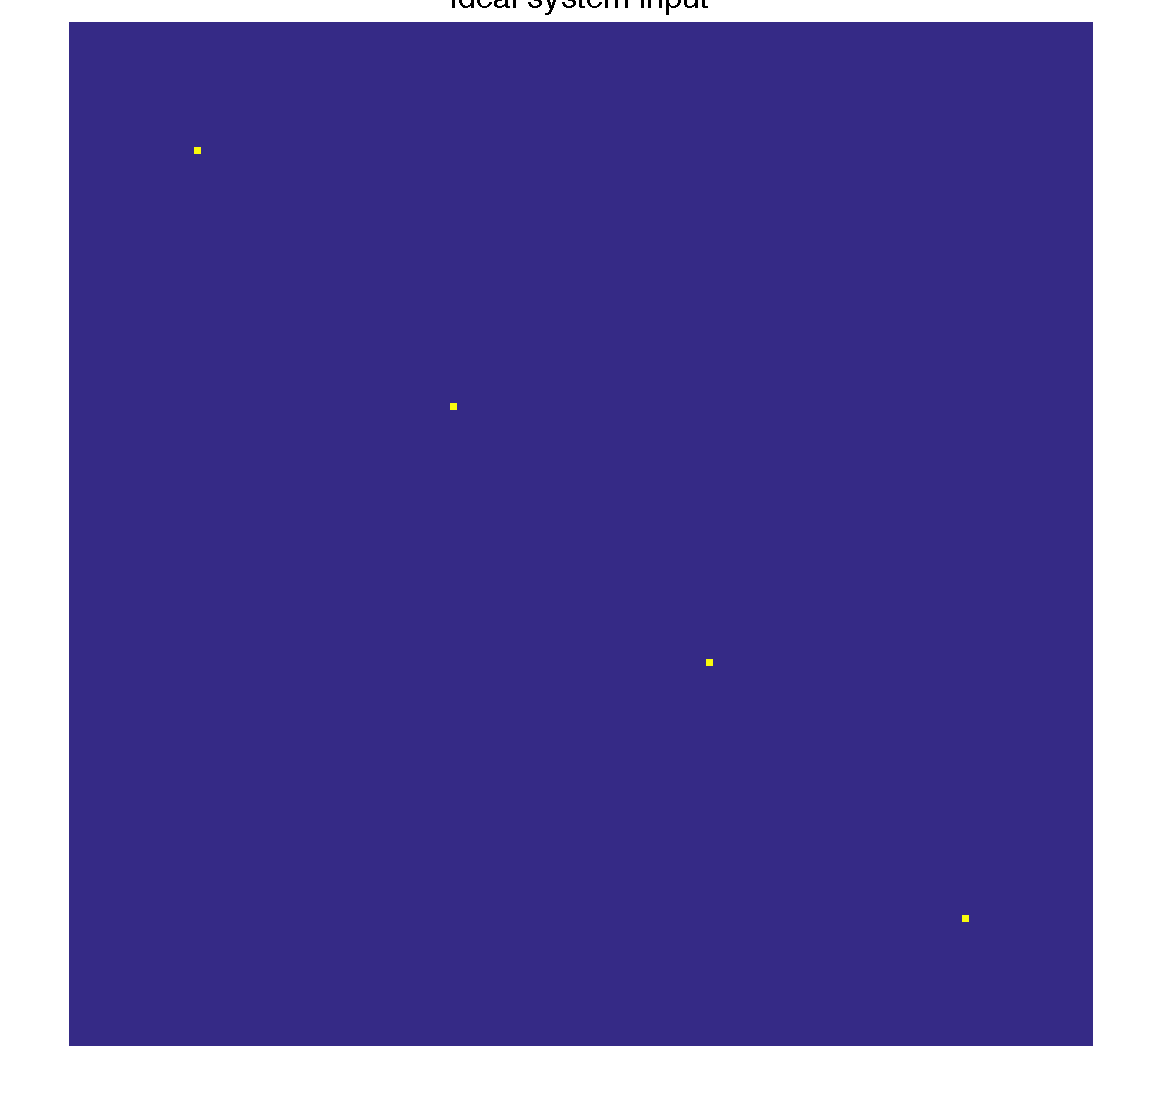

Simulate ideal system input

The ideal system input is a patch in each active temporal coefficient

mask = ones(ny, nz, T); TPSF_ideal = tpsf(mask, basis, K, patch_size); figure(1); imshow3(TPSF_ideal), colormap('default'); ftitle('Ideal system input', 32);